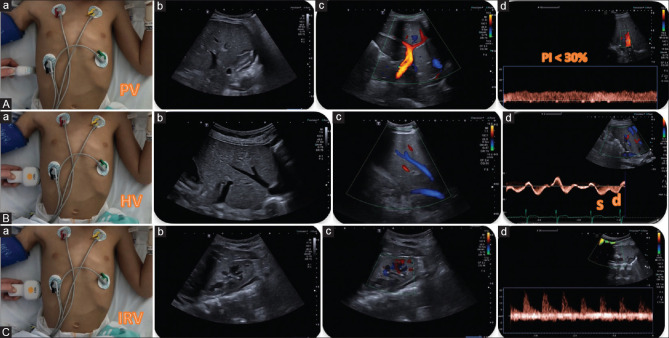

Effective fluid management presents a significant challenge for pediatric intensivists. Enhanced ultrasound data that predict adverse outcomes, such as edema and venous congestion, can provide important information about optimal fluid management. The integration of bedside multiorgan ultrasound protocols (Multi-POCUS) mitigates the limitations of individual scoring systems, enabling more accurate fluid monitoring and management. The Tri-POCUS approach, described initially in adult patients, combines lung ultrasound, focused cardiac ultrasound, and venous excess ultrasound, and its application in the pediatric population is proposed. This study examines the Tri-POCUS approach from a pediatric perspective: we applied it to a cohort of critically ill pediatric patients with venous congestion admitted to a pediatric intensive care unit. Four cases are presented to demonstrate the bedside utility of the Tri-POCUS approach in critically ill children with the goal of monitoring venous congestion.